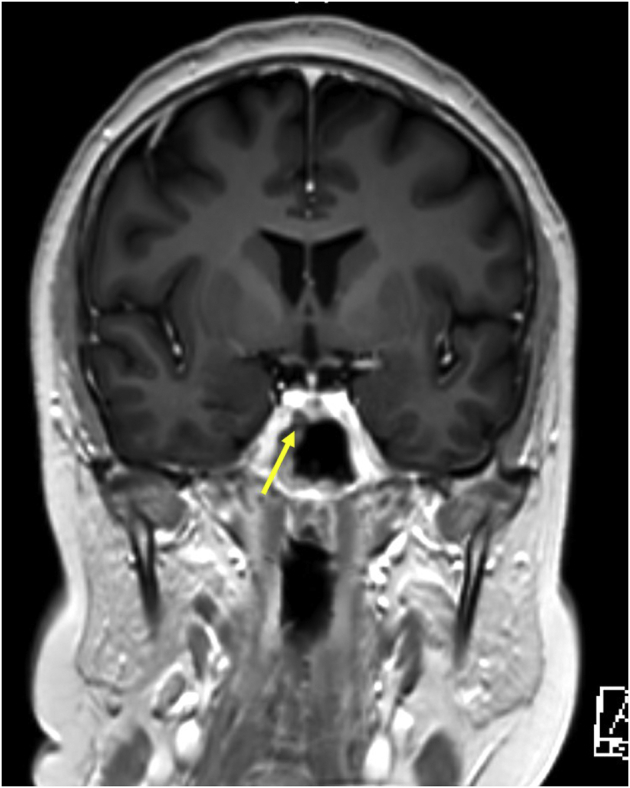

Fig. 2.

Bilateral avascular necrosis (AVN) of hips in Cushing disease. This patient’s hip x-ray showed ill-defined mixed sclerotic and lytic pattern of the femoral heads with cortical disruption of the round contour, typical of bilateral AVN of the hip. AVN is graded by radiologists using the Ficat classification in 4 stages, which in this patient was stage 2A on the right and stage 3 on the left. MRI of the hips showed low signal intensity in the subchondral region of the femoral necks on T1 weighted images, and MRI of the pituitary showed a hypoenhancing lesion measuring 2.5 mm × 2.5 mm, adjacent and inferior to the right cavernous internal carotid artery. She was started on medical management with ketoconazole, with which her hypercortisolemia was controlled, and was scheduled for stereotactic radiosurgery because of the proximity of the lesion to the right cavernous internal carotid artery. Expert opinion of the consultant orthopedic surgeon was sought and she was planned for total hip replacement at a later date in view of her young age. Decompression was not attempted as she had presented late with osteonecrosis and the benefit of surgery was uncertain. Bisphosphonates (parenteral zoledronate) were administered in view of low bone mass with a Z-score of −3.9 at the femoral neck and −3.5 at the lumbar spine. The prevalence of AVN of the hip following exogenous Cushing syndrome ranges between 3% and 38%.1 The Ficat classification (4 stages) is widely used for diagnosis and staging of AVN of the femoral head. Stage 1 is pain in the groin secondary to ischemia without radiographic changes. Stage 2 disease presents with radiological signs of increased density (2A) or mixed sclerotic and lytic pattern (2B). Stage 3 is characterized by disruption of the normal round contour of the femoral head, and stage 4 presents with complete collapse of the femoral head into a flattened contour, and decreased joint space.2 Bilateral AVN hip in endogenous Cushing syndrome is rare, and only few documented case reports are available to date.3 The exact mechanism of AVN in endogenous Cushing syndrome is not known. Fat-cell hypertrophy and vascular compromise, mini-fractures induced by glucocorticoids, osteocyte apoptosis, and intravascular thrombosis are the few proposed mechanisms for hip AVN.1,4 A multidisciplinary approach, with control of Cushing syndrome and orthopedic fixation is required for treatment.